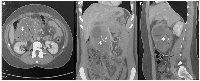

Laboratory tests, including tumor markers, were within normal limits. Carcinoembryonic antigen was less than 0.50 ng/mL, and carbohydrate antigen 19–9 was less than 3 U/mL. Abdominal ultrasonography revealed a large solid–cystic mass arising from the pancreas. Contrast-enhanced abdominopelvic computed tomography (CT) demonstrated a lobulated mass in the pancreatic head measuring 11.6 × 8.5 cm in axial dimensions and 7.2 cm in height. The lesion contained solid, cystic, and calcified components. It was in close contact with the duodenum, the splenomesenteric confluence, and the right colic flexure, without evidence of invasion (Figure 1). Magnetic resonance imaging (MRI) confirmed a large pancreatic head mass measuring 12 × 7.7 cm. The tumor showed mixed solid, cystic, and calcified components. It abutted the right colic flexure and the inferior vena cava, without biliary or pancreatic ductal dilatation. Overall, the imaging findings were most suggestive of a solid pseudopapillary neoplasm of the pancreas.

Figure 1

Contrast-enhanced abdominal CT of a large retroperitoneal mass.

The well-defined mass exhibits heterogeneous enhancement with scattered calcifications. ( A ) Axial view shows the lesion (asterisk) measuring approximately 8.2 × 11.8 cm. ( B , C ) Coronal (B) and sagittal (C) reconstructions demonstrate the craniocaudal and anteroposterior (8.6 cm) extent of the mass, respectively, and its displacement of adjacent abdominal structures.

Figure 1: Contrast-enhanced abdominal CT of a large retroperitoneal mass.